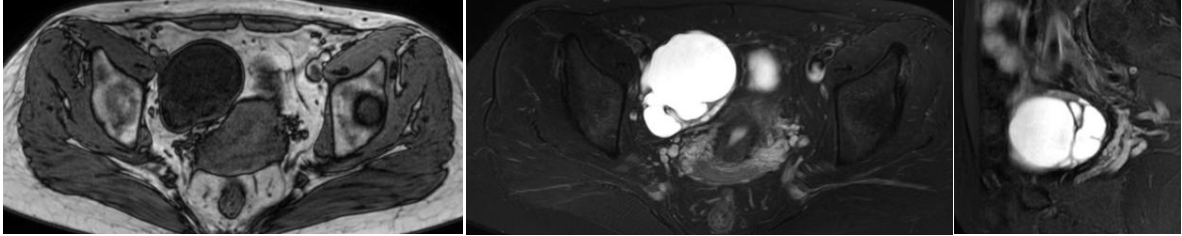

多有痛经史,发病年龄偏小,病灶可多发,囊肿大小不一,大囊周边伴小囊,形成“卫星囊样”改变,由于囊内出血,T1WI多呈高信号,T2WI随出血时间信号不一,部分囊内可见液平。

本院病例:25岁,因排卵期出血入院;病理:双侧卵巢子宫内膜异位囊肿

本院病例:36岁,体检发现盆腔包块7年余;病理:右侧卵巢黏液性囊腺瘤

鉴别诊断----卵巢透明细胞癌(OCCC)

OCCC以囊实性多见,且大部分OCCC的前驱病变为子宫内膜异位症,囊内可有出血,呈T1WI高信号,因此需于SO鉴别,OCCC多表现为宽基底乳头状、结节状赘生物突入囊腔,多数偏心性生长同时伴有邻近囊壁增厚,典型表现为单房囊性肿块伴单个或多个大小不等实性壁结节,且实性结节弥散受限。

本院病例:53岁,已绝经,们及腹部肿块2天,肿瘤标志物阴性;病理:透明细胞癌